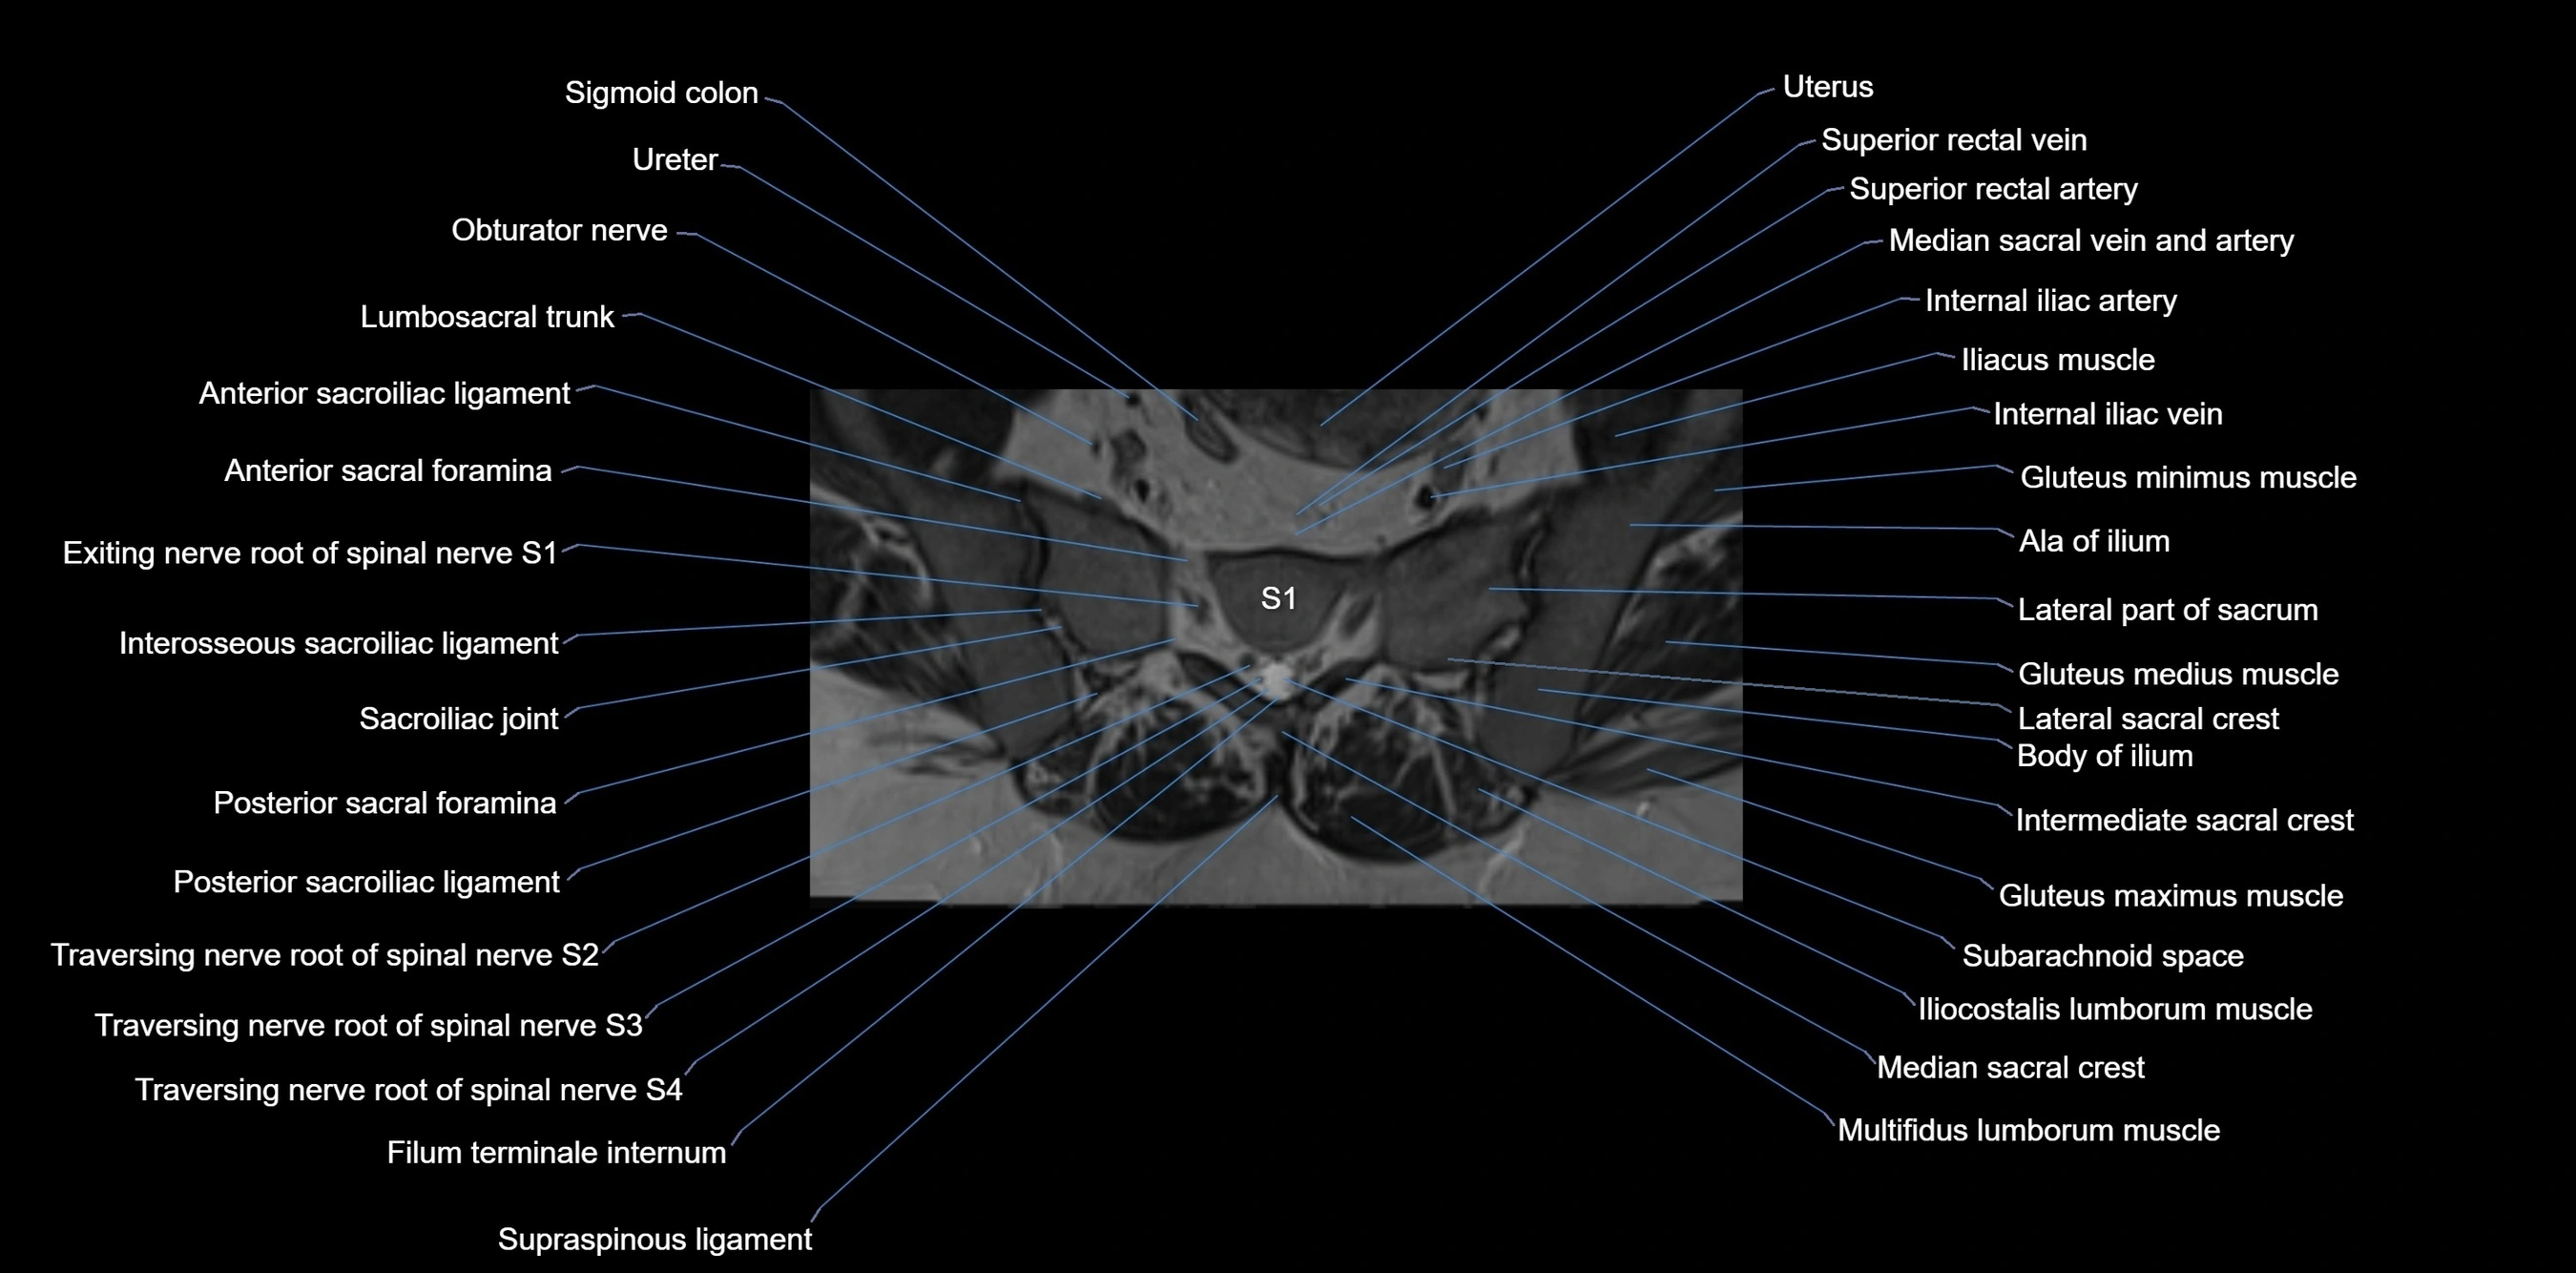

CT VRT image

image